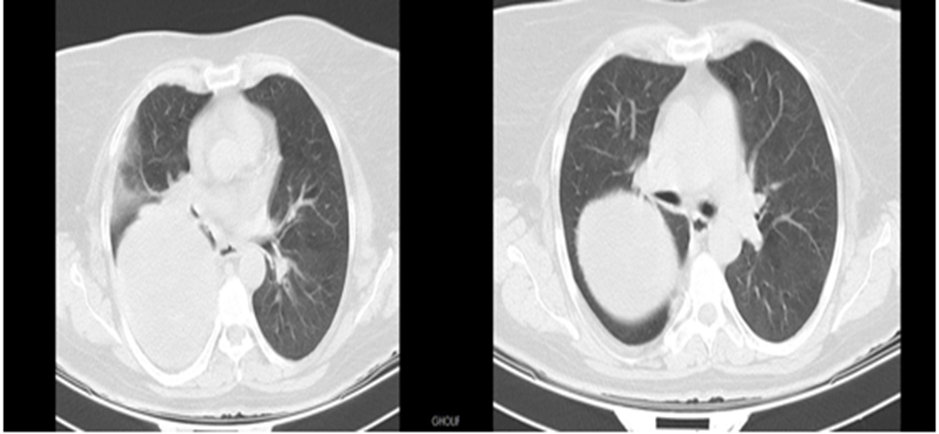

A 58-year-old woman was refered to our hospital with a history of recurrent right side chest wall pain ,cough ,night sweating ,hemoptysis and dyspnea for 4-6 weeks. A physical examination revealed respiratory sounds were decreased on the middle right side of chest. His complete blood count, erythrocyte sedimentation rate, CRP blood urea nitrogen (BUN) level, and creatinine level were normal and liver function tests (AST,ALT ,AKP and bilirubin ) and anti hydatid tests were normal . Poster anterior (PA) and lateral chest radiographs were performed . The PA chest radiograph (Figure 1)showed a well-defined 10- to 14-cm right paracardiac cystic mass located in the right middle zone of chest. The CT-scan showed a large well –defined hypo dense cystic mass measuring 112 mm is seen in superior segment of RUL.Sub segmental atelectasis also seen in right lung caused compressing. Left lung was normal . Figure 2(a,b,c,d,e,f,g,h,i) . In the CT –scan there was no invasion of the chest wall and others intrathoracic structures. CT images show no enlargement of lymph nodes and pleural effusion but lung parachymal was involved.The testes for hydatid cyst were negative .Ultrasonography of abdomen was normal . A classic right posterolateral thoracotomy in six intercostal space was performed. Around of cystic lesion was walling off with wet sponge with normal Saline (Fig 3). In the aspiration of the lesion there was a hemorrhagic dense viscous fluid .The cystic mass was completely removed without complications and free margin. On the operation time , macroscopic examination show hemorrhagic dense viscous fluid and debris was observed in the center of the lesion(Fig 4) Microscopic examination showed an encapsulated mesenchymal neoplasm composed of short fasciles of bland looking spindle cell which are diffusely positive for S100 and GEAP on immunohistochemically diagnosis was a schwannoma tumor. The patient was discharged on the 6 th postoperative day. The patient did not recurrence after 8 month of follow-up

Figure: 2 CT -scan A, B, C, D, E, F, G show solid cystic lesion.